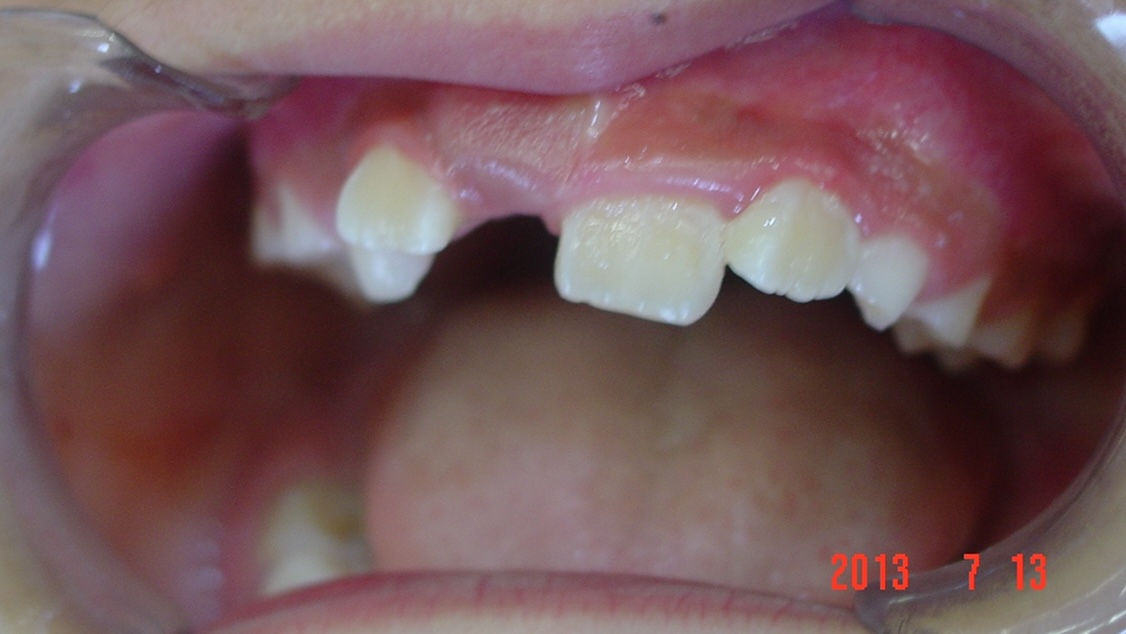

矯正前

| 症状 | 左上2番3番逆転症例 |